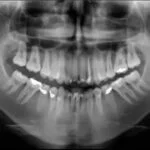

Cone Beam Case Study:  Abscess on #24

Cone Beam Case Study:  Obturation of #13